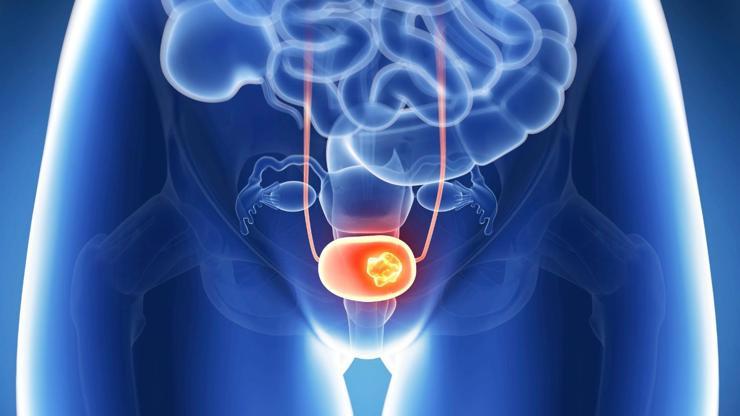

Mesane tümörleri nasıl tedavi edilir?

Mesane, böbreklerden süzülen idrarı depolayan ve vücut dışına atılmasını sağlayan organımızdır. Mesanenin iç yüzeyi hücre tabakasıyla örtülüdür. Mesane kanserlerinin yaklaşık olarak yüzde 90’ı, bu hücrelerin kontrolsüz bir şekilde çoğalmasıyla ortaya çıkar. Üroloji Uzmanı Prof. Dr. Mustafa Sofikerim, mesane tümörleri tanı ve tedavisini sizler için anlattı.

Mesane kanseri teşhisinde, hekiminizin alacağı tıbbi öykü ve yapacağı fizik muayenenin ardından, en sık kullanılan tanı yöntemi sistoskopidir. İdrar yolundan ince ışıklı bir aletle girilerek mesanenin içinin görüldüğü sistoskopide, gerekiyorsa şüpheli dokulardan parça alma olanağı da bulunmaktadır.

Kanserin mesane ile sınırlı kalmasını sağlamak için anestezi altında yapılan bir pelvik muayene ile mesaneye bir sistoskop yerleştirilir ve tüm üretra ile mesane değerlendirilir.

Yapılan testlerin sonucuna bağlı olarak hastalığın derecesi ve evresi belirlenir. Tedavi şekline belirlenen evre ve dereceye göre karar verilir. Mesanenin kas dokusuna kadar ilerlemediği saptanan ve düşük dereceli hastalıkta sistoskopi eşliğinde yapılan TUR operasyonuyla kanserli doku çıkartılabilir. Kimi zaman, uygun durumlarda, bu işlem tanısal amaçlı yapılan sistoskopi esnasında bile gerçekleştirilebilir.